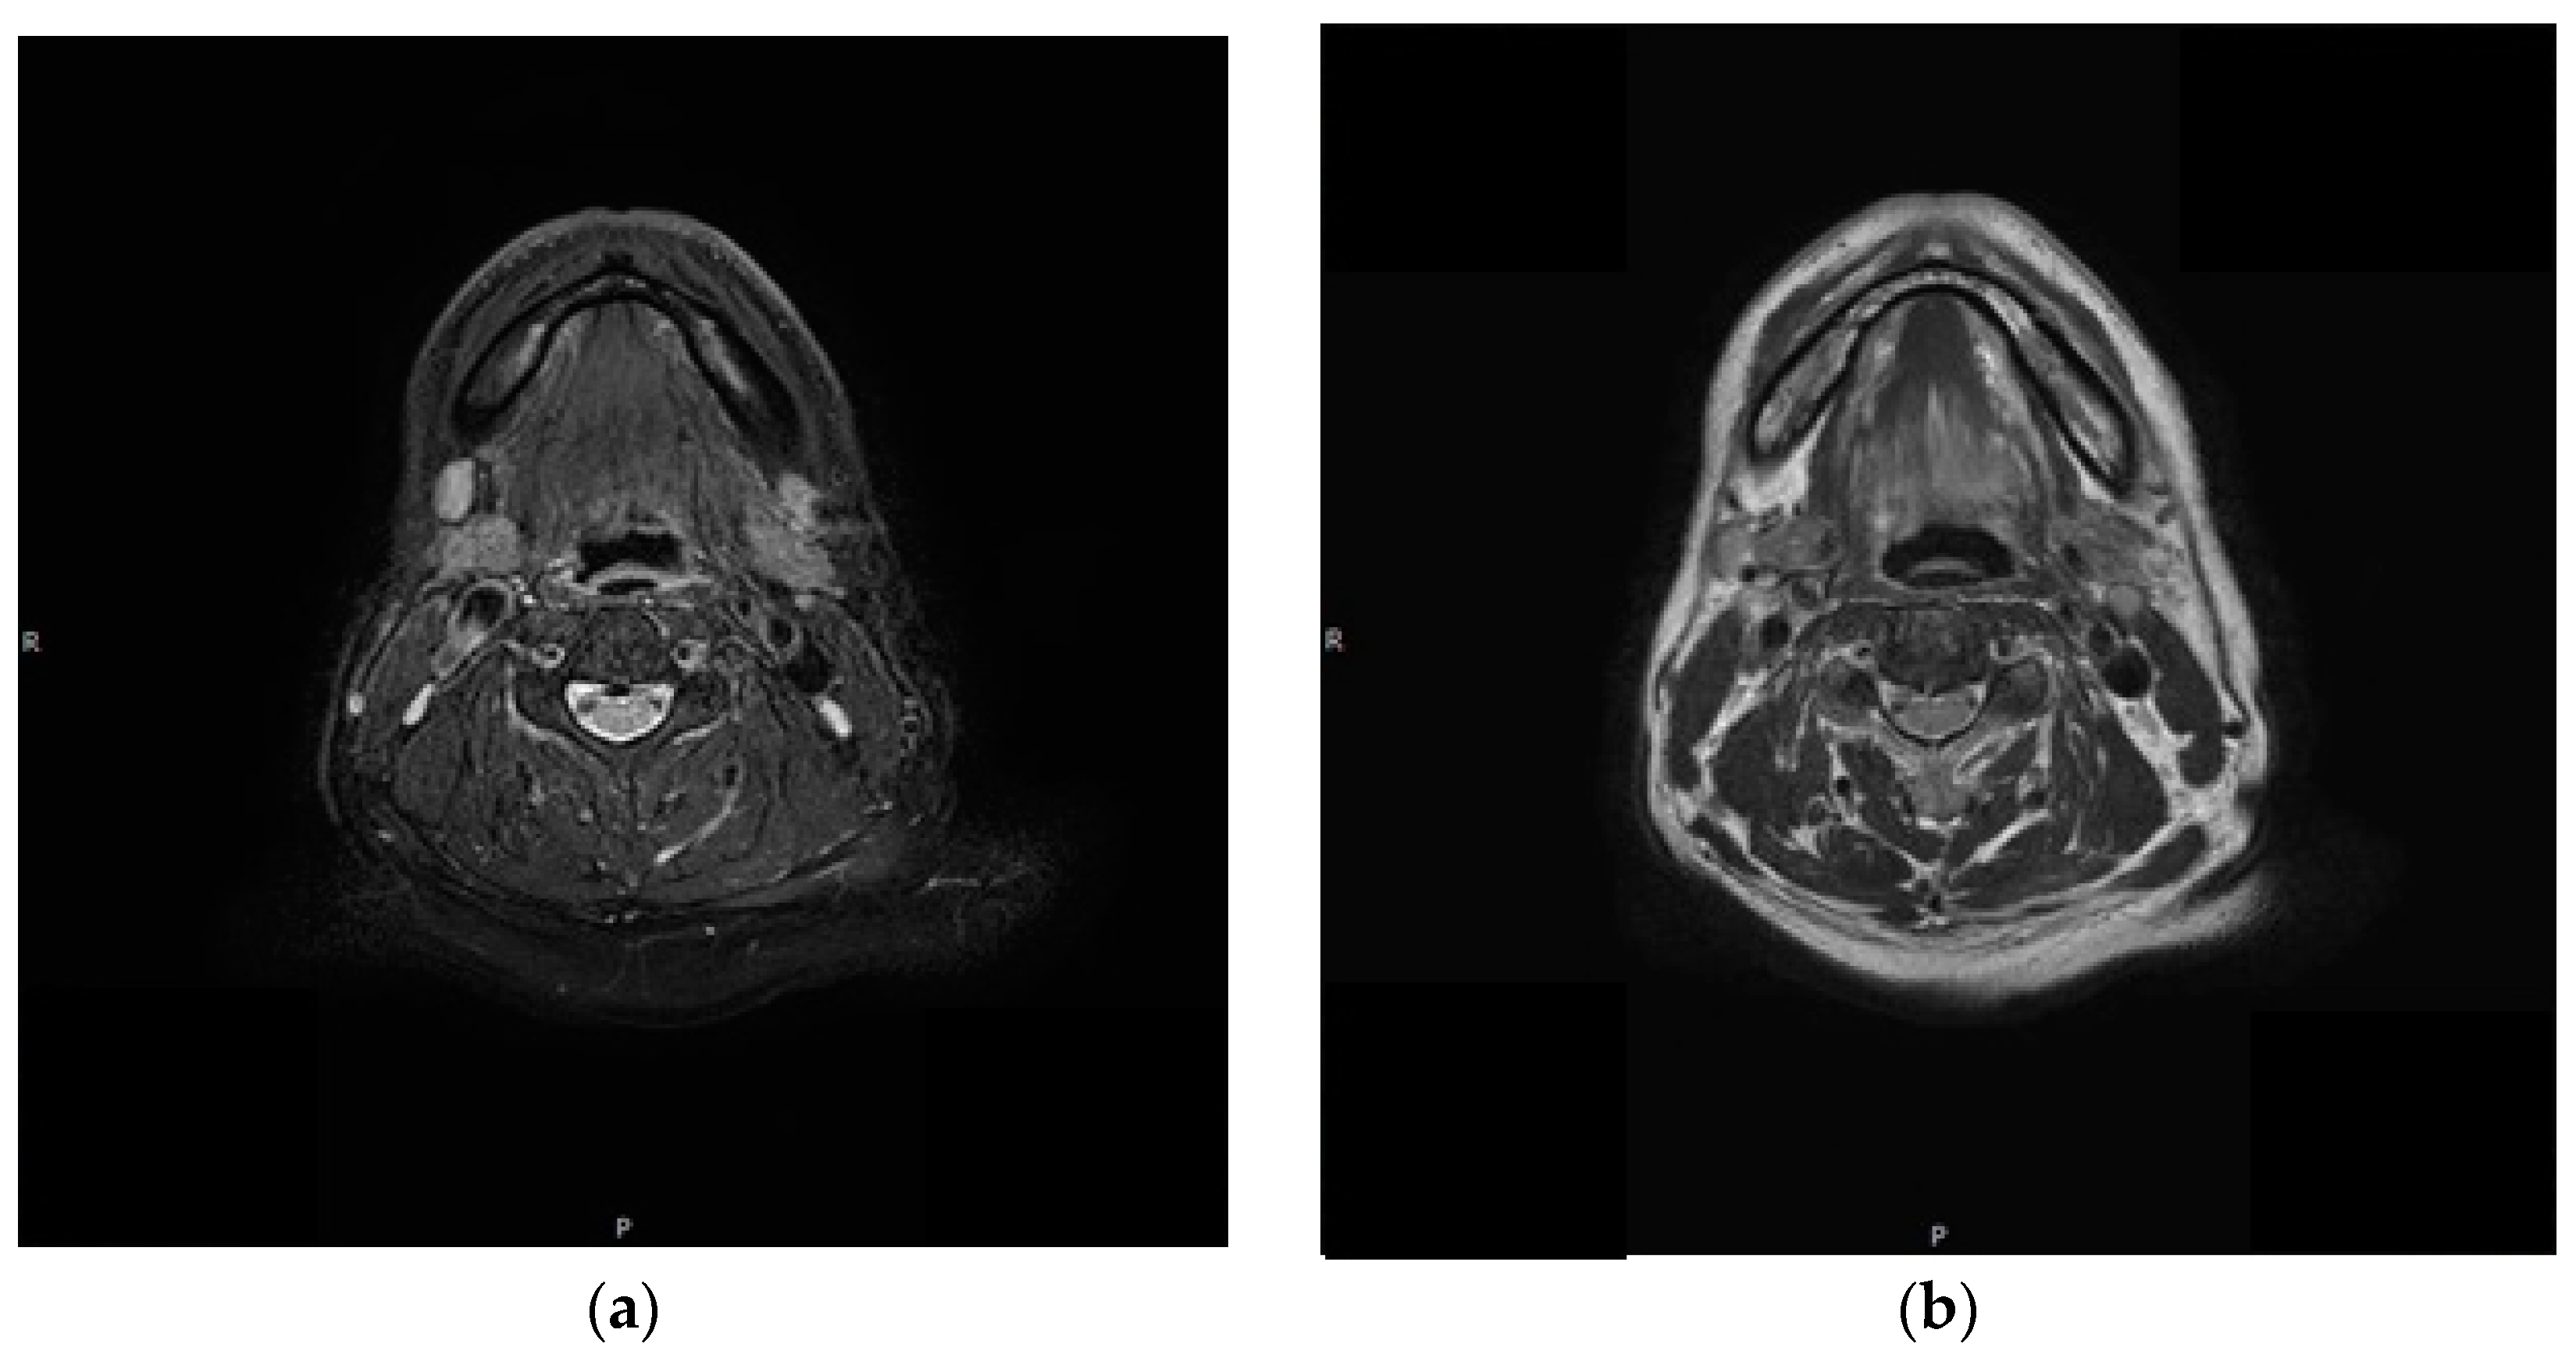

2. Case Report